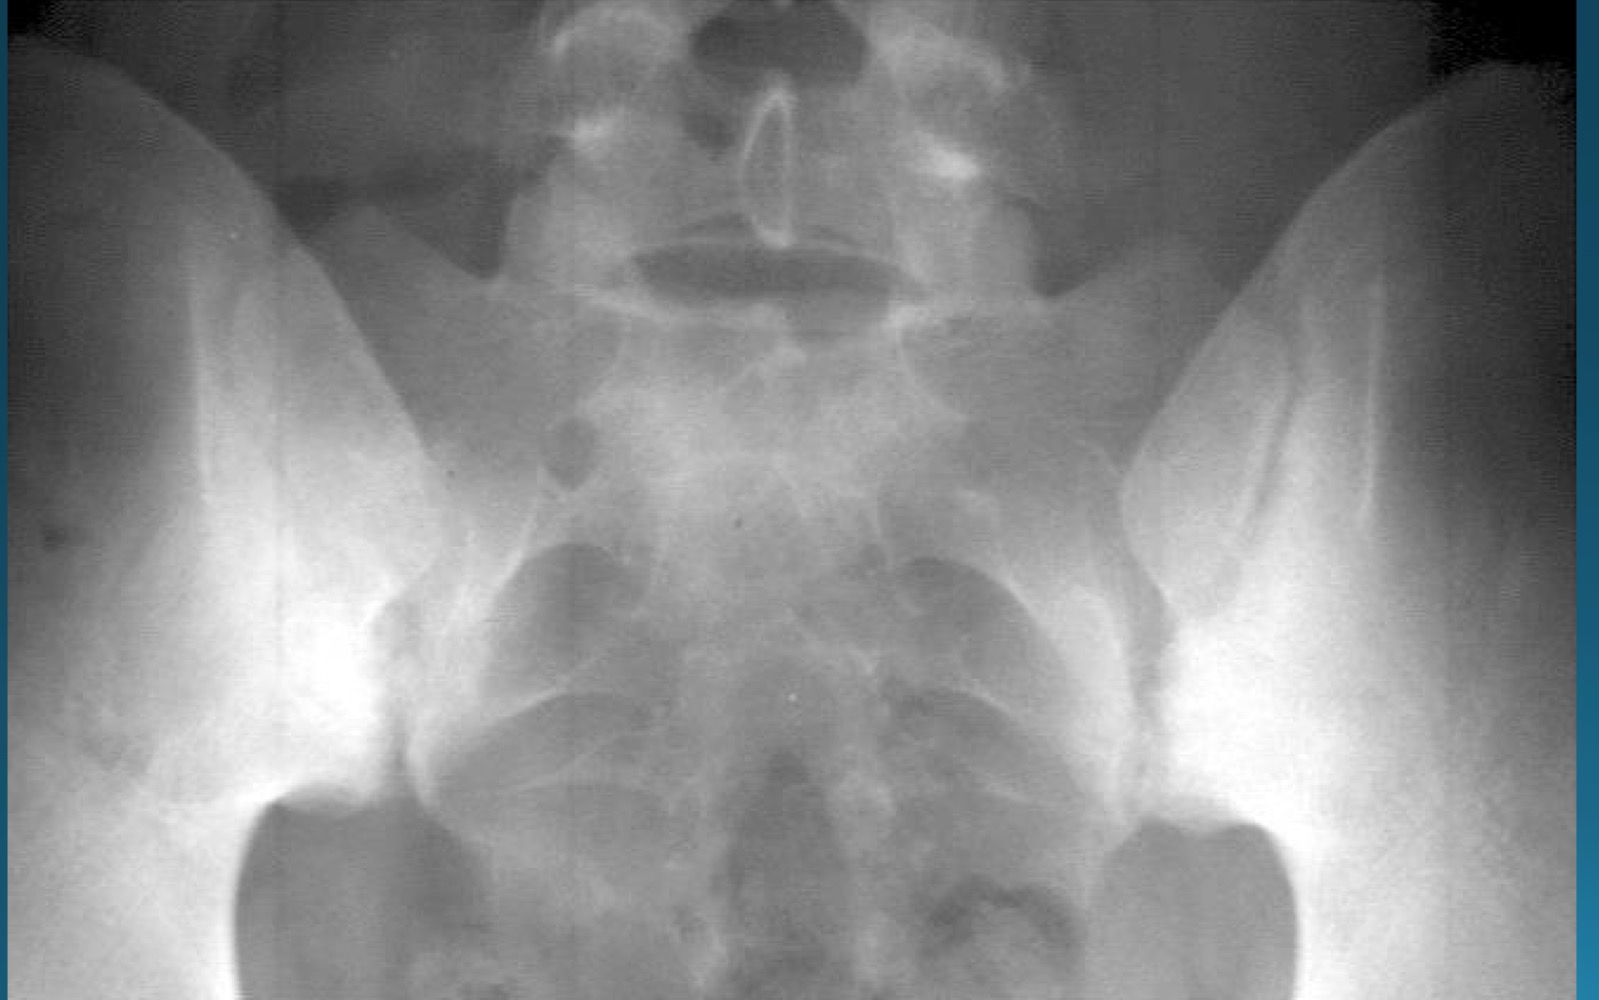

what is the diagnosis?

AS

sacroilitis

what are the signs seen in this image? what diagnosis would you make

rosary bead appearance (wavy appearance in SI joint area)

star sign (at superior angle of SI joint)

what are the signs seen in this image? what diagnosis would you make?

ghost joint (line in SI joint area but no space)